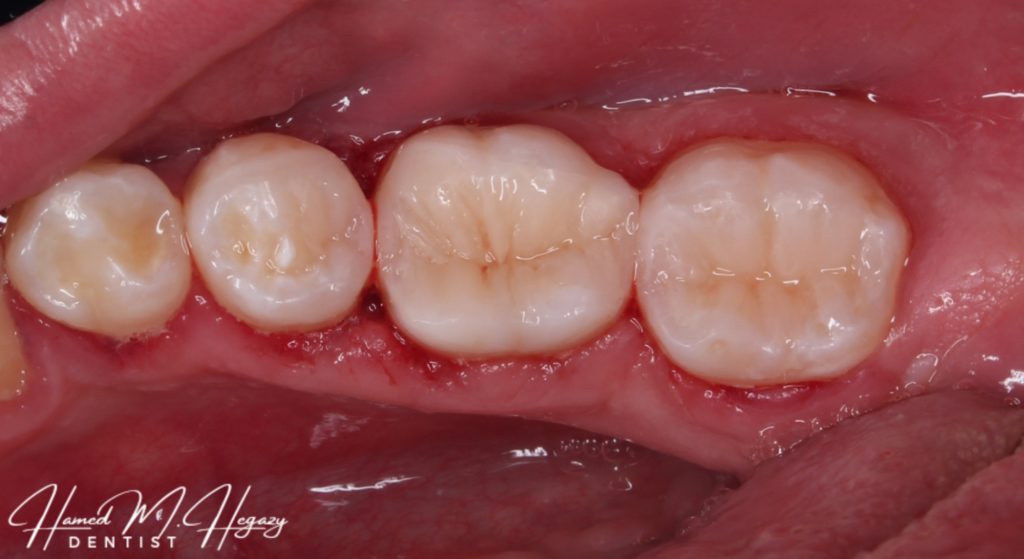

Another view

Final look